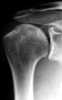

Traumatic osteochondral injury

Microfracture surgery is an articular cartilage repair surgical technique that works by creating tiny fractures in the underlying bone. This causes new cartilage to develop from a so-called super-clot. [Source: Wikipedia ]